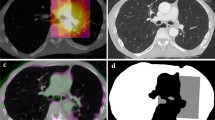

A dose monitoring system (Radimetrics, Bayer HealthCare, Leverkusen, Germany) provided patient information, age, sex, and scanner radiation output in terms of DLP11. The system also calculated with Monte Carlo methods organ doses (\({OD}_{T}\)) for 25 organs (\(T\)). Several metrics were calculated to perform the analysis (Table 2). The DLP-based effective dose (\({E}_{DLP}\)) was calculated multiplying the DLP by the anatomical region conversion factors for adult patients reported in Table A.2 of the ICRP publication 1021. Moreover, following the ICRP publication 103 tissue weighting factors, \({E}_{OD}\) was calculated per each patient6. The radiation risk index (\(RI\)) was estimated by applying the sex- and age- specific lifetime attributable risk of cancer incidence in the US population for the tissue \(T\) (\({r}_{T}\)) reported in BEIR VII to the patient-specific organ doses (\(OD_{T}\)): \(RI = \mathop \sum \limits_{T} r_{T} OD_{T}\)5,12,13. Lastly, the updated relative effective dose \({(E}_{r})\) was calculated adjusting \({E}_{OD}\) for an age and sex patient-specific factor \(f=\frac{RI}{{RI}_{rp}}\), where \({RI}_{rp}\) is the risk index calculated for a 35-year-old reference patient considering sex-averaged \({r}_{T}\) coefficients: \(E_{r} = f \times E_{OD}\)10. We tested the null hypotheses of no relationship between \({E}_{DLP}\), \({E}_{OD}\), and \({E}_{r}\), and \(RI\), each. For each metric, mean, median, range, and standard deviation were further calculated.